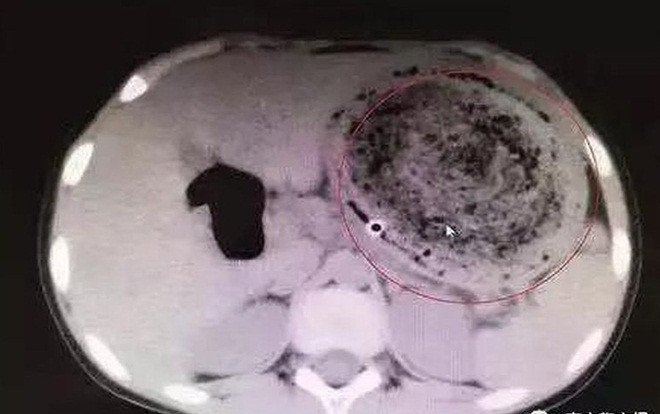

Bác sĩ đã rất ngạc nhiên khi chụp CT và phát hiện một búi tóc khổng lồ lẫn với cặn thức ăn. Tuy nhiên, búi tóc to bằng quả bóng này không thể được loại bỏ thông qua nội soi vì có dấu hiệu vôi hóa.

Hình ảnh búi tóc rối trong dạ dày của Phi Phi.